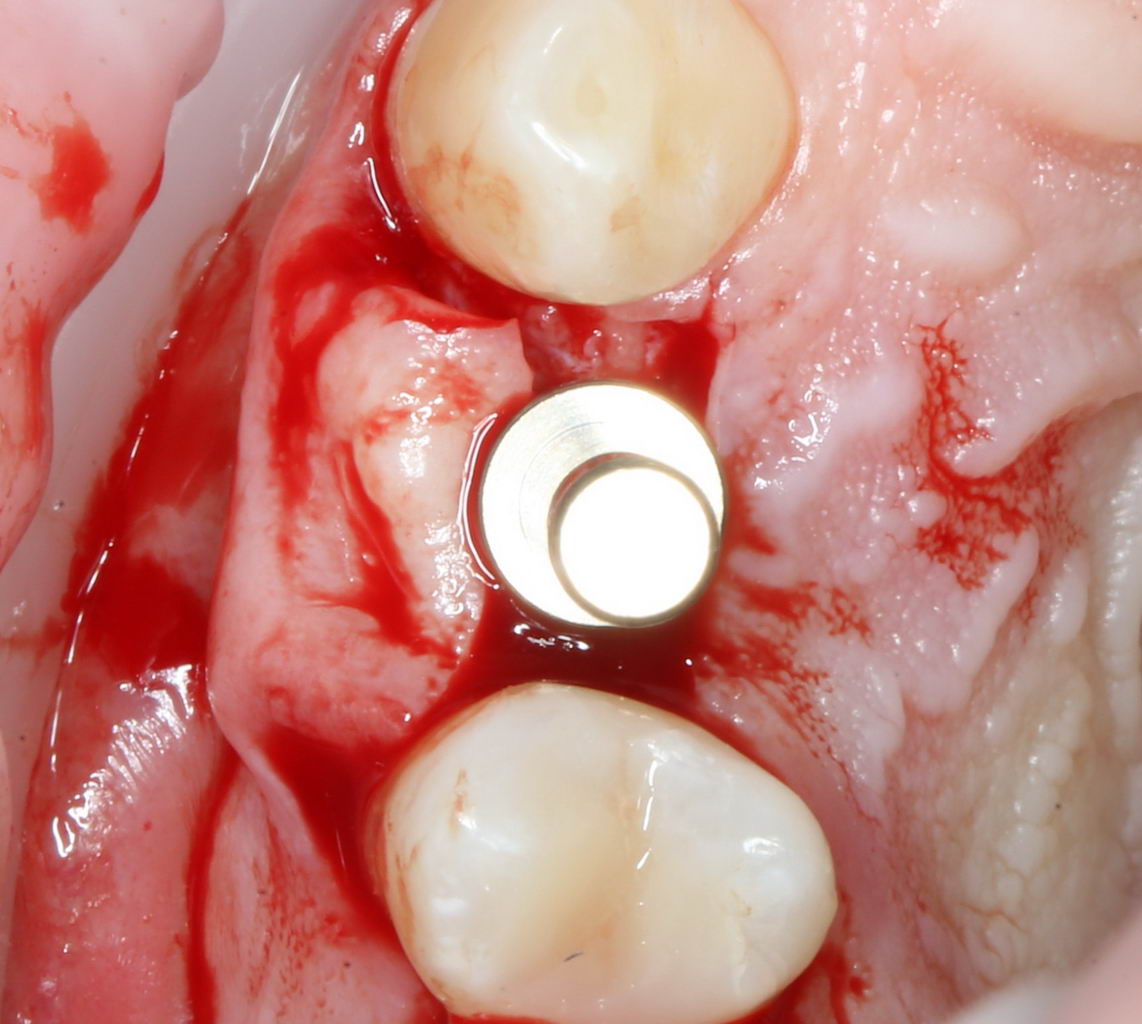

И, коль всё в порядке, переходим к следующему этапу операции — установке формирователя десны.

Установка формирователя десны.

Одномоментная установка формирователя десны позволяет сократить время и удешевить лечение — ведь по мере интеграции имплантата мы получаем нормально сформированный контур десны, готовый к установке протетической конструкции. Но это возможно лишь тогда, когда с объемами мягких тканей в области имплантата всё в порядке. То есть, как раз в нашем случае.

В CLINIC IN используют только одноразовые формирователи и только один раз:

С учётом клинических условий, мы подобрали к установленному имплантату формирователь Slim (без расширений) высотой 3 мм: